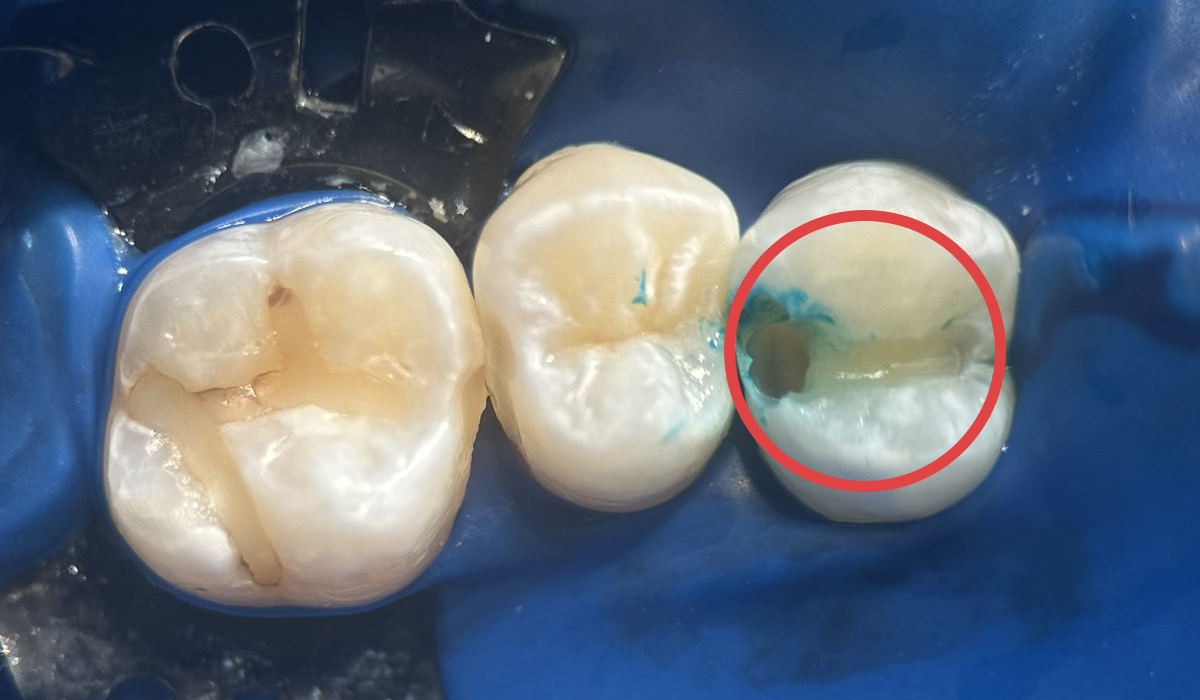

- 虫歯の詰め物

虫歯の治療後今まで銀歯を被せていたケースも、ダイレクトボンディングを用いて自然な歯になりました。